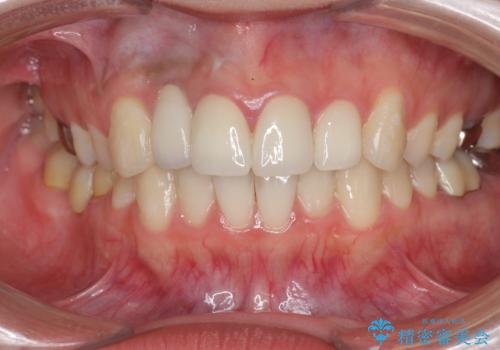

充填されたコンポジットレジン・再発した虫歯を神経に影響が出ないよう丁寧に除去し再充填をしたのちオールセラミッククラウンで前歯の審美性を回復します。

- 33万円(仮歯・ジルコニアクラウン×3)費用は治療当時の料金となります

前歯のコンポジットレジン修復は、経年劣化し虫歯の再発しやすい素材なので定期的なX線検査が推奨されます。